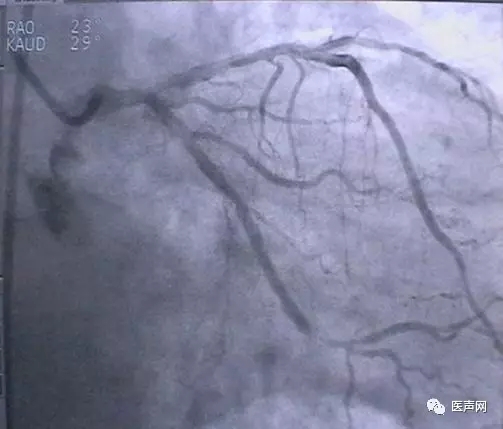

病例1: 冠脉搭桥术后,静脉桥CTO(CABG, VB-CTO)

箭头所示为第3个吻合点

(pre-PCI)

VB-对角支(jump)---LCX(jump)-PDA远端,第一个吻合以下完全阻断。

· 导引导管非常深置(Very very deep seating)(本例GC达CTO 第一吻合口前)(这是Dr. Lauer常用一招)

· 对侧造影

· 硬导丝(走得很远, 达PDA)

· 微导管,OTW 球囊.

当打通后,发生室速,电复律---出现无复流---室速---植入支架(TAXUS Liberte)

当导引导管非常深置(very very deep seating)时,你可以想象支持力有多大,永远不要忘记他做RCA-CTO时导引导管深插到RCA中段的例子。此病例实际上PDA未能开通,在6月28日 Dr. Lauer终于用类似方法打通了PDA。